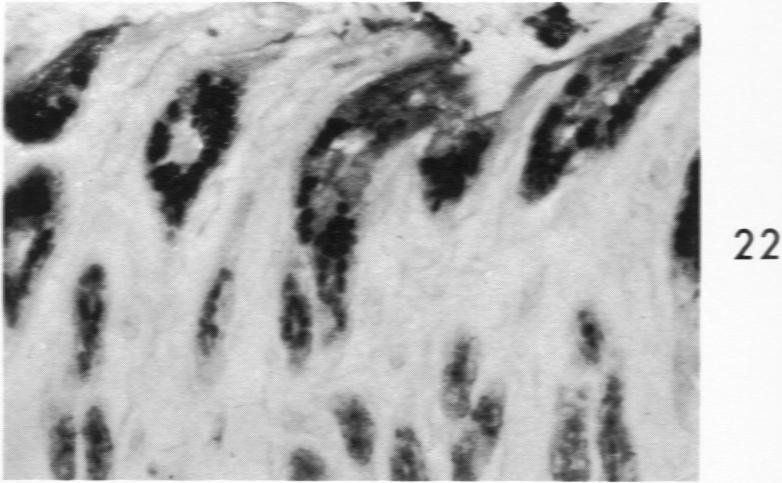

Histochemical and morphologic changes in gastric mucosa of dogs on ulcerogenic regimen.

Am J Pathol. 1969 Jul;56(1):129-51.